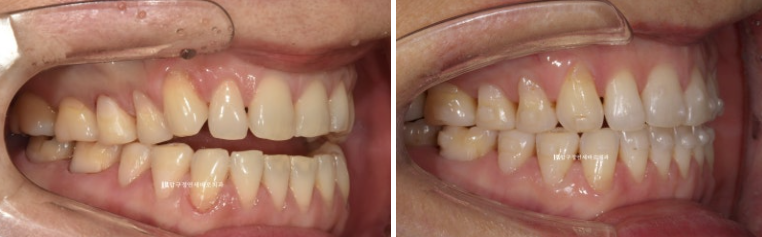

23.05~23.12

걱정하시는 교합도 잘 마무리 되었습니다.

추가장치의 목적은 미세하게 안 맞는 중심선을 맞추고 교정 후 어느정도 재발될 것을 예상해서 살짝 과개교합 상태를 만들어 놓는 것입니다.